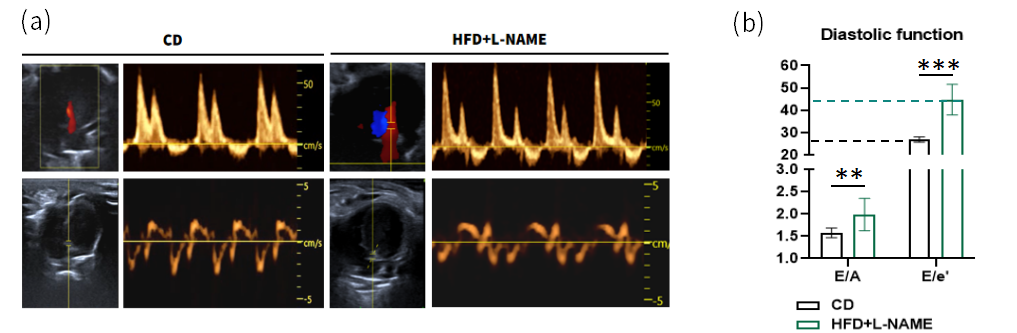

心脏舒张功能受损

心脏四腔切面超声评估结果显示(图3),与普通饲料对照组(CD)相比,HFD+L-NAME组小鼠表现出显著的舒张功能障碍。具体表现为:E/A比值(反映心室早期充盈与心房代偿收缩的流速比)与E/e'比值(评估心室充盈压的指标)均显著升高,提示小鼠心室僵硬度增加且主动松弛功能受损。

图3. 心脏四腔切面超声结果

(a) 心脏脉冲多普勒和组织多普勒示例图;(b) E/A 比值(左室舒张早期与舒张晚期二尖瓣血流速度比值)与 E/e' 比值(左室舒张早期二尖瓣血流速度与二尖瓣肌肉环运动速度比值)统计分析。 数据以 Mean±SD表示,每组n=8。**表示p<0.01, ***表示p<0.001。